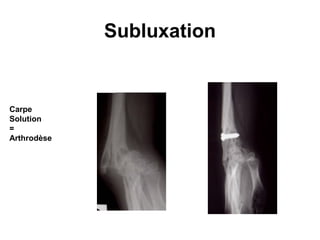

Radiologiques :

   Poignets et mains : c'est au poignet que

sont observés de façon caractéristique

les quatre stades classiques successifs

de STEINBROCKER :

   I- Ostéoporose, infiltration des parties

molles et appositions périostées.

   II - Pincement articulaire.

   III - Erosion

   IV- Fusion.

Forme avec présence

de facteur rhumatoïde,

ayant débuté à l’âge de 6 ans   .

A. 1 an d’évolution    B. 3 ans d’évolution :

: ostéoporose          ostéoporose,                C. 5 ans d’évolution : bloc

mineure.               pincements articulaires,    carpien presque complet.

irrégularités des points

d’ossification.

Subluxation

Carpe

Solution

=

Arthrodèse